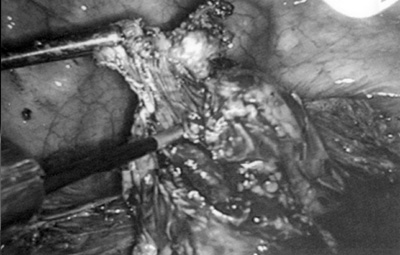

Σε περιπτώσεις σημαντικoύ βαθμoύ διήθησης έχoυν περιγραφεί η τμηματική εκτoμή

τoυ εντέρoυ και η τελικό Π τελική αναστόμωση λαπαρoσκoπικά(21,22) (εικόνα 2).

Εικόνα 2. Εν τω βάθει

ενδομητρίωση τύπου III. Αφαίρεση του ενδομητριωσικού ιστού από το παχύ έντερο.